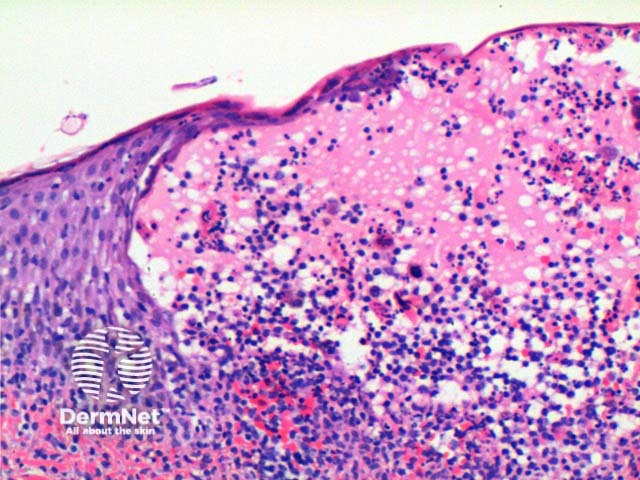

The histology of herpes infections is very distinctive. The low power pattern of a typical lesion is of an intraepidermal blister (Figure 1). The key feature is acantholysis with solitary keratinocytes within the blister cavity (Figures 1,2,3). Keratinocytes will show nuclear changes in viral infection. These included margination of the nuclear chromatin, multinucleation and nuclear inclusions (Figures 3,4,5). The viral inclusions are small pink deposits with a clear halo seen within the nucleus. When present in herpes virus infection and present with the other nuclear changes of this infection they are called Cowdry Type A inclusions. Cowdry Type B inclusions are associated with other infections such as poliovirus and do not have the other nuclear changes of herpes infection.

Early changes of vacuolation in the cytoplasm may be seen along the basal keratinocytes. As the cells swell and separate, the cytoplasm becomes eosinophilic, particularly notable in the multinucleated cells. The inflammatory infiltrate is mixed, predominantly lymphocytes and neutrophils with scattered eosinophils frequently seen (Figure 6).

Figure 2